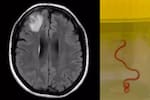

En la colonia Los Jardines, a 40 minutos del municipio de Simojovel, en el estado de Chiapas, muchas familias se dedican a recolectar, cocinar y comercializar un gusano que los lugareños consideran un manjar: el zats (arsenura armida) que en la lengua tzotzil significa gusano.

El agricultor de maíz y café Silverio Gómez Jiménez, de origen maya-tzotzil, es un recolector y desde niño se ha dedicado a buscar este gusano que se alimenta de los árboles de caucho.

El gusano aumenta su población durante el verano, exactamente en los días más calurosos de junio, julio y agosto, que son los ideales para la recolección en los municipios de Chilón, Ocosingo, Huitiupan, Simojovel y Yajalón, que se ubican al norte de Chiapas.